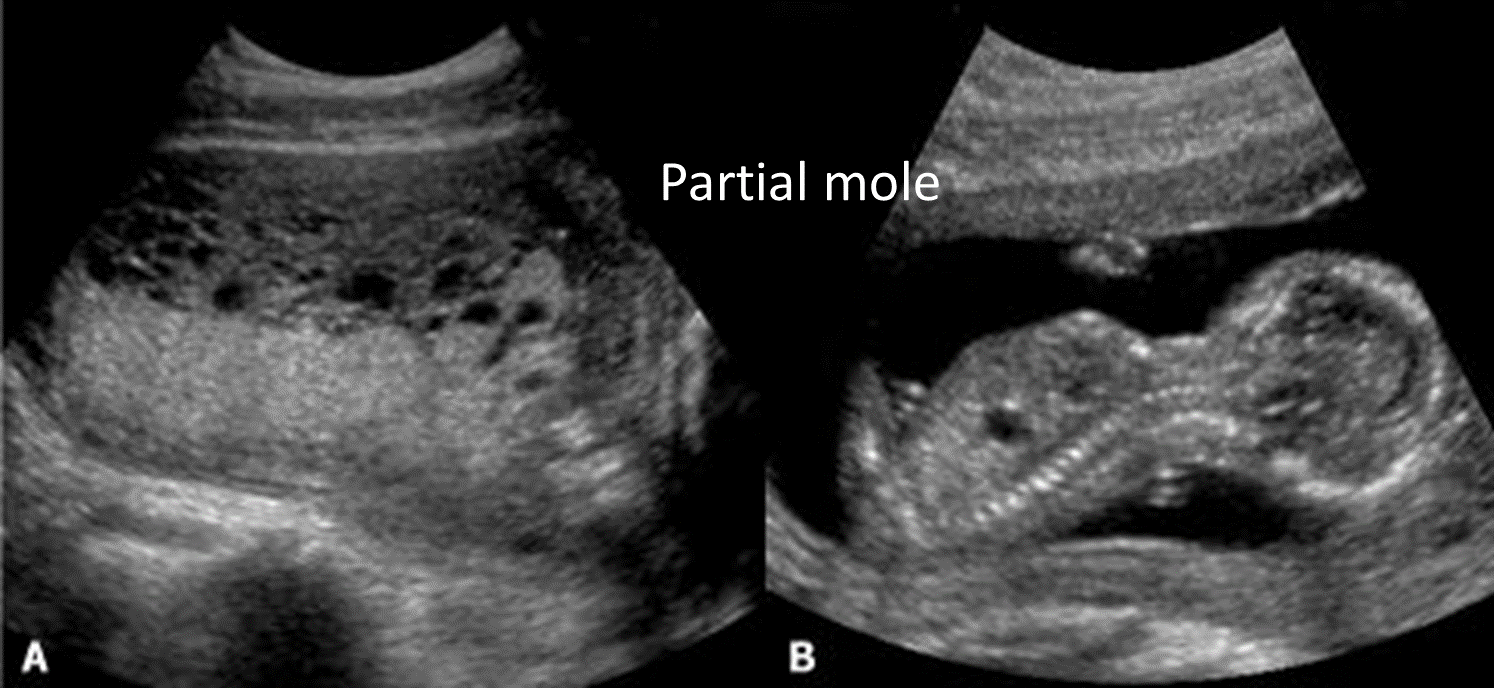

1. Partial molar pregnancy

- Fetal parts may be visualized.

- Fetal heart tones may be detectable.

- Amniotic fluid is present.

- Increased placental thickness

2. Complete molar pregnancy

- Echogenic mass interspersed with many hypoechogenic cystic spaces referred to as “swiss cheese”, “honeycomb”, “bunch of grapes”, or “snowstorm”)

- No amniotic fluid

- No fetal parts

- Lack of fetal heart tones